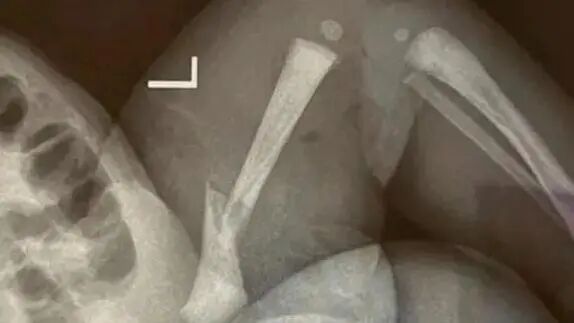

据此前报道,4月中旬,人民医院内一名婴儿在剖宫出生后一直大哭,并未得到医护人员重视。第二天在集中洗澡时,医护人员才发现孩子腿部红肿,此时已经过去16小时。经检查确诊骨折,后续孩子的伤处甚至有溃烂情况。张先生称,专家建议保守治疗,且不能保证正常发育,以后可能会出现长短腿,O型腿。

对此,靖江市人民医院给央广网的回应是:确有其事。这次事件医院有责任,是手法不熟练导致的,但这并不是一起医疗事故,是常见并发症。后医院也协助将孩子送至南京市儿童医院进行治疗。